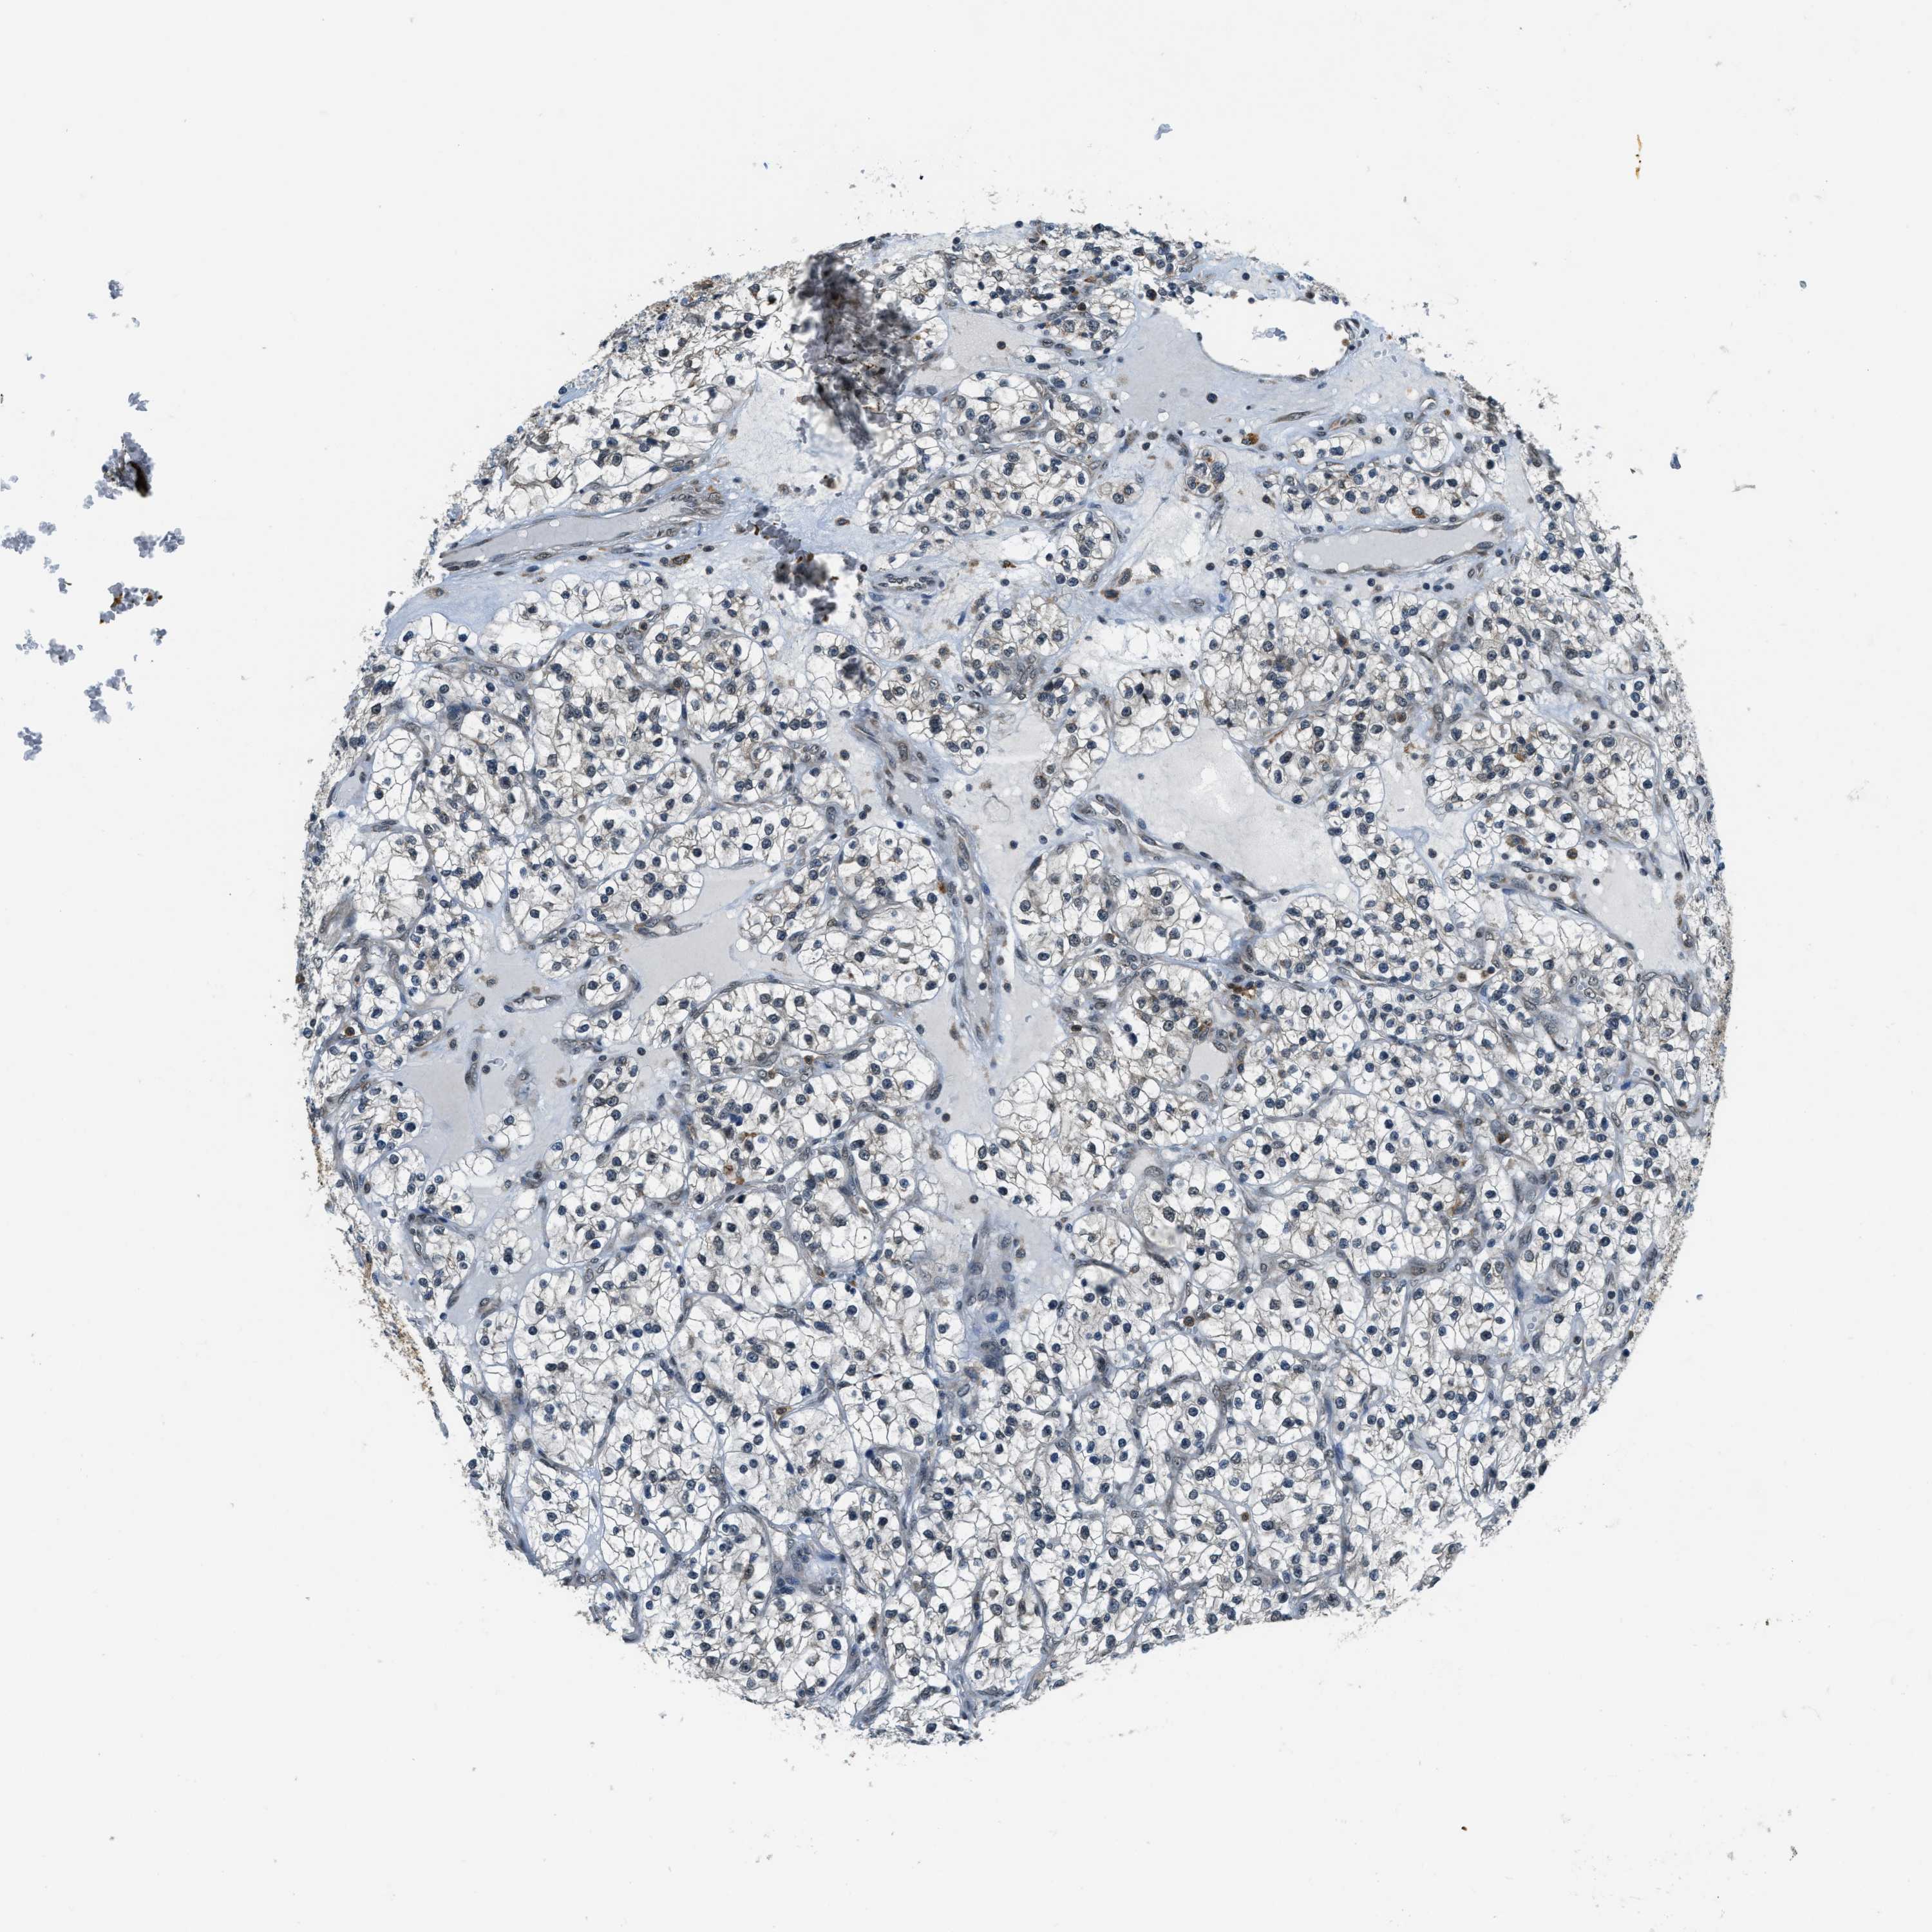

CANCER RENAL CANCER Show tissue menu

KICH TCGA KIRC TCGA KIRC VALIDATION KIRP TCGA PROTEIN RCC CPTAC PROTEIN EXPRESSION

Kidney chromophobe